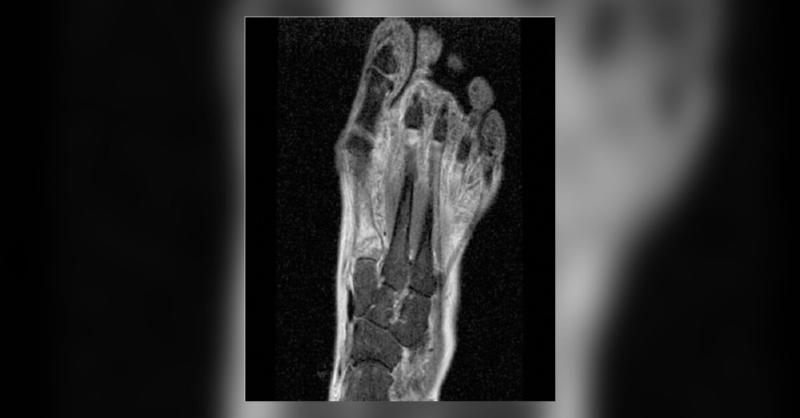

Running Gone Wrong- Metatarsal Bilateral Stress Fracture in a Middle-Aged Woman

A 52-year-old female presented with a complaint of bilateral forefoot pain that has persisted for the past two weeks. The onset of her symptoms had begun after a 20 km run in an amateur race, a distance exceeding her usual 10 km weekly routine as an amateur runner. She also noted that the pain intensified during walking or jumping but subsided at r